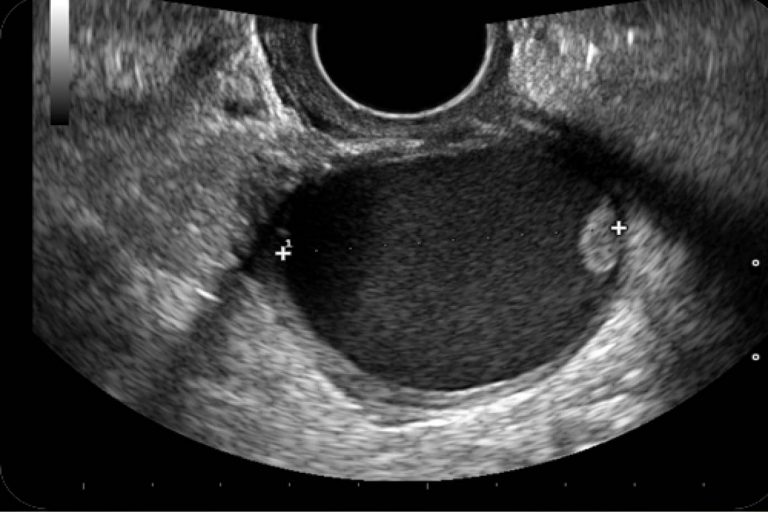

Diagnóstico imagenológico de un teratoma gigante de ovario

Teratoma ovarico ecografia 2D 3D Dr. Rafael Ortega Muñoz Ginecologo Ciud... Ecografia